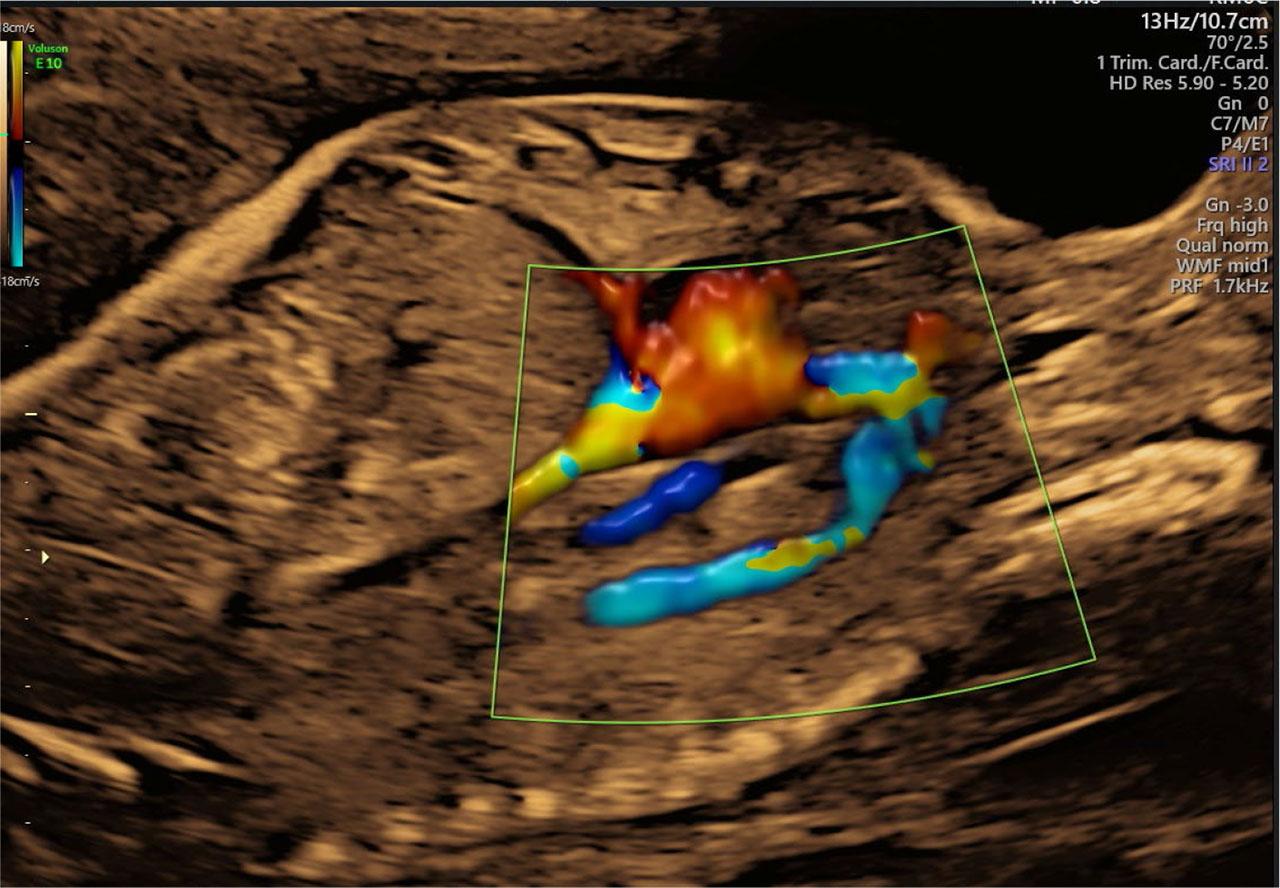

Fig. 2.